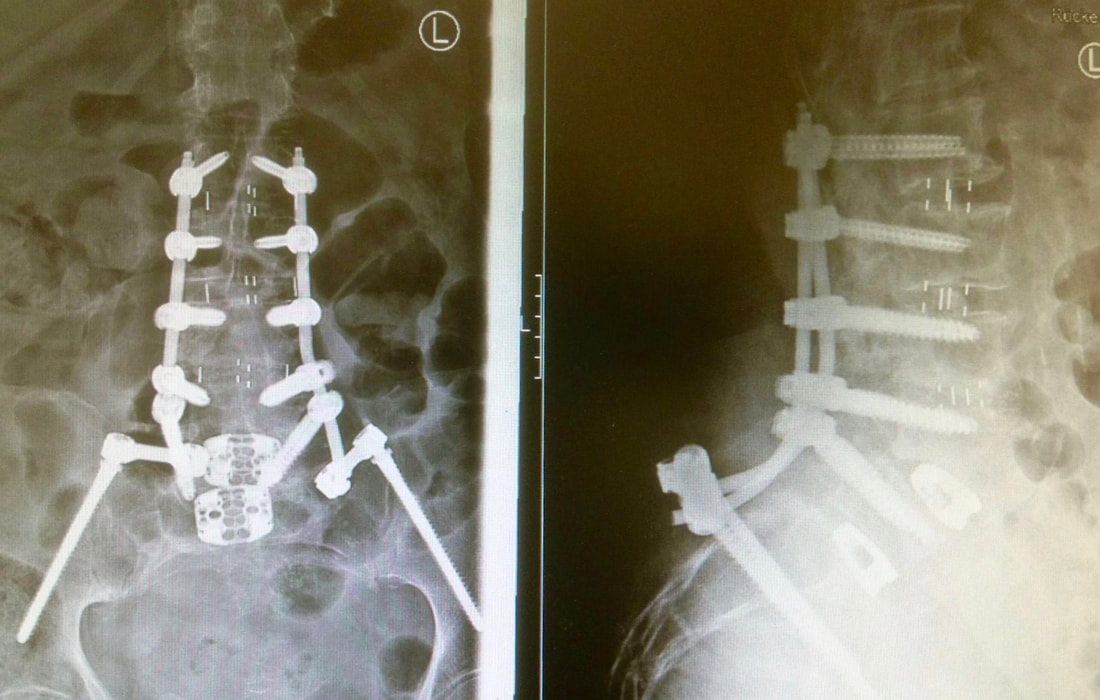

Un traitement est nécessaire lorsque le spondylolisthésis entraîne des douleurs importantes ou une baisse de la qualité de vie. Les traitements non chirurgicaux comprennent une modification des activités afin de diminuer les charges/forces sur la colonne vertébrale, la physiothérapie, des médicaments ou des injections pour diminuer la douleur. Quand le traitement conservateur ne fonctionne pas, et que les douleurs ne sont plus supportables, une chirurgie de stabilisation par fixation et fusion (spondylodèse) est proposée.

Des vis sont implantées dans deux ou plusieurs vertèbres afin de fixer l’instabilité. Une ou plusieurs cages sont également placées entre les vertèbres, une fois le disque intervertébral retiré pour permettre une fusion.

Le traitement va dépendre du type de fracture et de l’atteinte neurologique. Il va du traitement conservateur par corset ou minerve à la fixation par des vis avec parfois une résection de la vertèbre fracturée et le placement d’une cage en titane. Parfois, une injection de ciment (cyphoplastie) suffit à stabiliser la fracture.